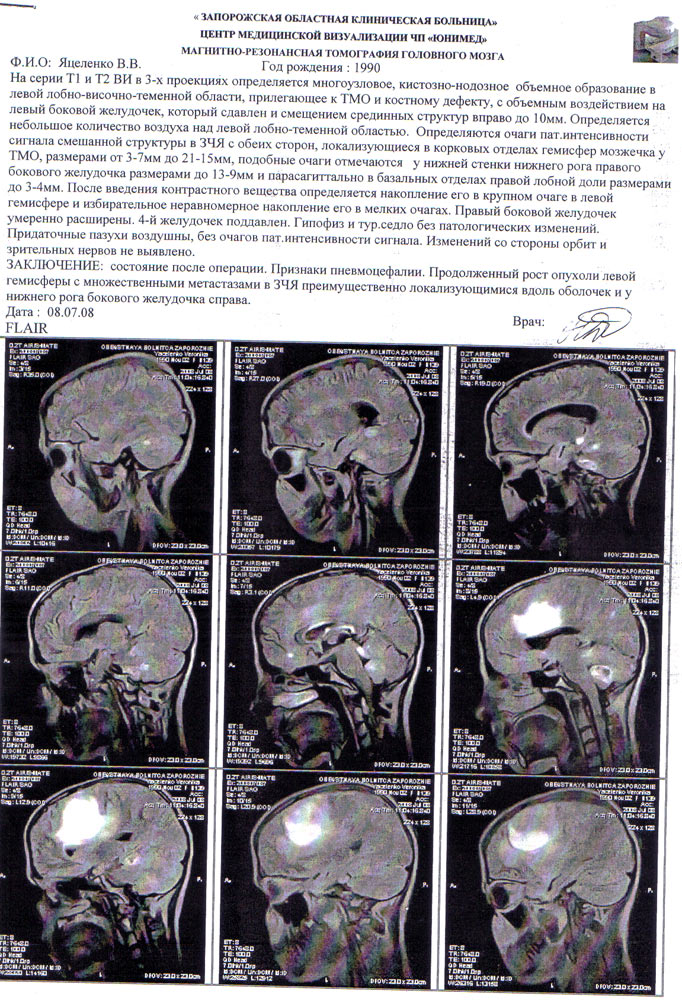

Диагноз: опухоль мозга (глиобластома 4 ст. злокачественности).

Результат МРТ томографии от 8 июля 2008 года

Год назад, в мае 2007 года Вероника вдруг начала жаловаться на частые головные боли, общую слабость, периодическую тошноту, рвоту, затруднение при выговаривании слов, шаткость при ходьбе, слабость в правых конечностях. При обследовании врачи обнаружили у девочки объемное образование в левой лобно-височной области головы. Опухоль удалили в Запорожской областной клинической больнице, по результатам гистологических исследований был поставлен диагноз: анапластическая менингиома...

Затем – послеоперационный период, лучевая терапия, большое количество сильнейших медицинских препаратов … казалось, все уже позади… Но вот симптомы вернулись – опять боли, слабость, головокружение… Повторное обследование – и опять как приговор: опухоль головного мозга, рецидив…По данным медицинской статистики, у 100% больных с анапластическими менингиомами рецидив после операции возникает в течение 3 лет.

Материал был направлен на паталогогистологическое исследование в Киевскую городскую онкологическую больницу врачу-паталогоанатому высшей категории Захарцевой Л.М. В результате исследования лимфома была исключена, а опухоль отнесли к глиобластоме.